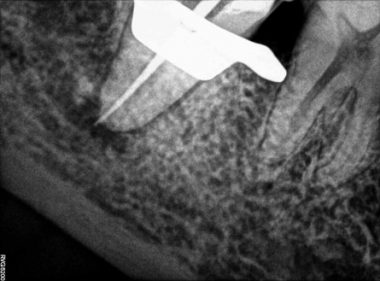

Patient Name: Asha Mane

Tooth Number: 47,48

Diagnosis: Radicular Cyst with 47,48

Treatment : endodontic treatment with 47, Extraction with 48.

File system used : TRUESHAPE 3D, Vortex Blue

Pre-operative

Obturation

After extraction with 48

Follow up after 3 months

Master cone after 1 month

Follow up after 6 months